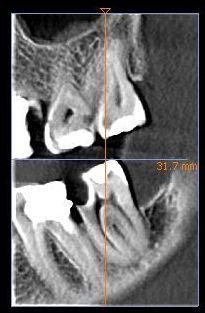

Вопрос такой есть ли смысл лечить и сохранять 8 зуб?

Был на консультации в 2 клиниках - вердикт удаление ( лечить не хотят.)

Говорят что пульпит и смысл лечения нет.

Просто смотрю растет правильно хотя уже есть пломба и большая кариозная полость.

Прошу прощения за качество снимка вытаскивал сам из КТ.